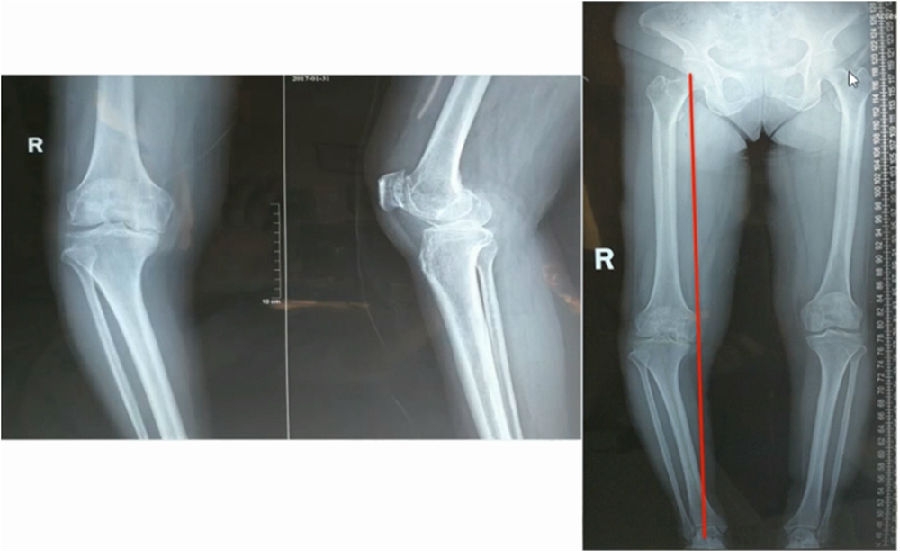

典型病例,女性,35岁,农民,左膝内翻、短缩、内旋。

术前

泰勒外固定架缓慢矫正短缩、内翻、前弓、内旋。

术中

该患者截骨后,做MAD矫正,目标MAD=0。患者术后1个月即达到设计的效果。

术后1个月

典型病例2,男性,52岁,双膝疼痛,低磷佝偻病,复合畸形。

股骨畸形即时矫正,胫骨畸形缓慢矫正。

手术前后对比